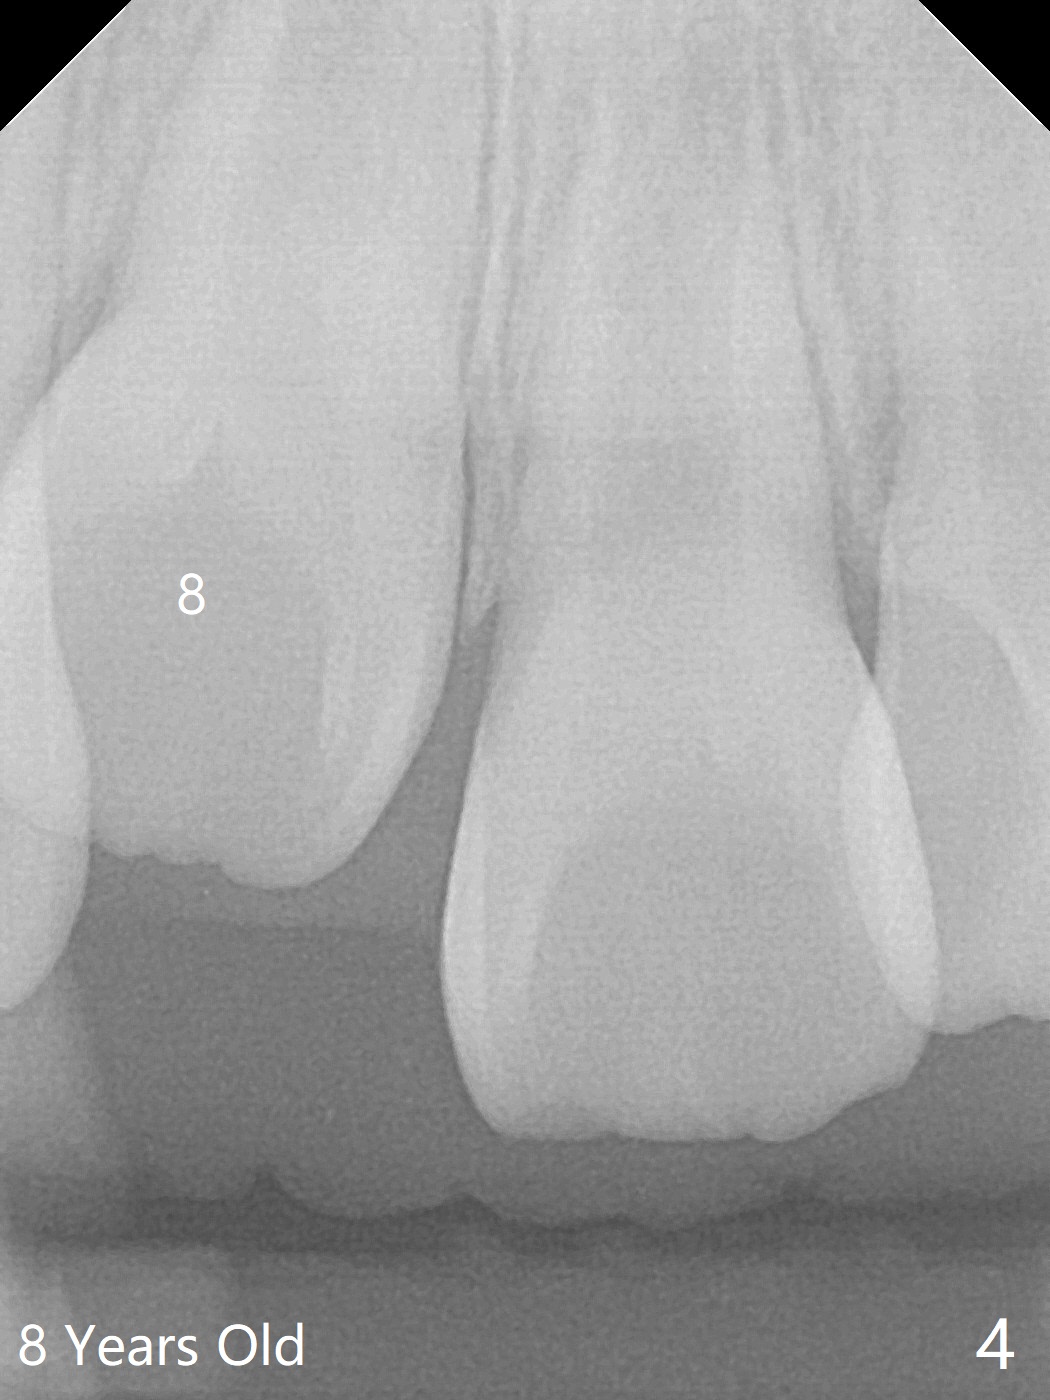

6岁女孩上中切牙发育萌出好像比侧切牙晚(图一),七岁时萌出顺序正常(图二),但是八岁时右上中切牙阻生(图三,四)。似乎拥挤是阻生原因,除了切开助萌之外,扩弓是必要的。不过她口腔卫生欠佳。